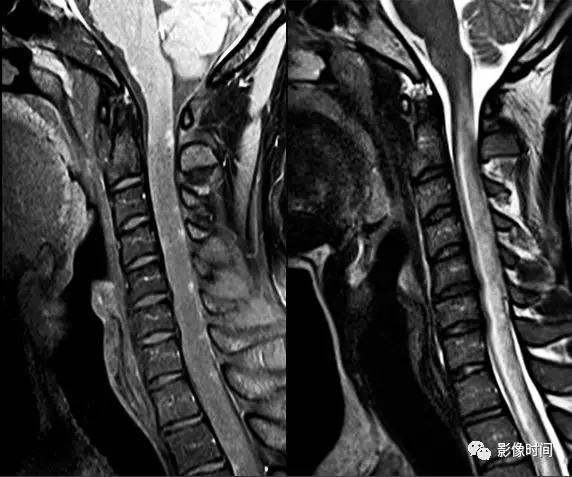

神经脊髓炎谱系疾病(neuromyelitis optica spectrum disorder,NMOSD):是一种由水通道蛋白-4(AQP-4)自身抗体介导的炎性脱髓鞘疾病,青年或中年女性较多见,临床常为双侧视神经炎和脊髓炎导致失明和截瘫,也可累及大脑。

MRI:

脊髓:病灶 T2WI 呈高信号,T1WI 呈稍低信号,急性期出现斑片状或云雾状强化,轴位常位于脊髓中央,长度>3 个椎体长度。亮点征:轴位 T2WI 很高信号的多发斑点,信号高于脑脊液,特异性=97%。

病灶分布于脊髓中央,长度大于3个椎体,亮点征

视神经:双侧视神经广泛受累,病灶长度通常>1/2 视神经长度,优先损害后视通路,包括视神经颅内段、视交叉和视束,急性期 T2WI 视神经肿胀伴明显高信号,T1WI 视神经明显强化,后视通路为主。

后视路受累为主,明显强化

多发性硬化(Multiple sclerosis,MS)亦是一种严重的中枢神经系统自身免疫脱髓鞘病变,免疫球蛋白分泌 B 细胞和浆细胞的克隆性扩增,可使 CSF 中出现寡克隆带特征。

脊髓:颈髓较常受累,病灶 T2WI 呈高信号,T1WI 呈稍低信号,轴位常分布于前索、侧索或者后索,长轴 ≤ 2 个连续阶段椎体,急性期呈斑片状、结节状或环形强化。

病灶位于侧索、长度小于3个椎体节段